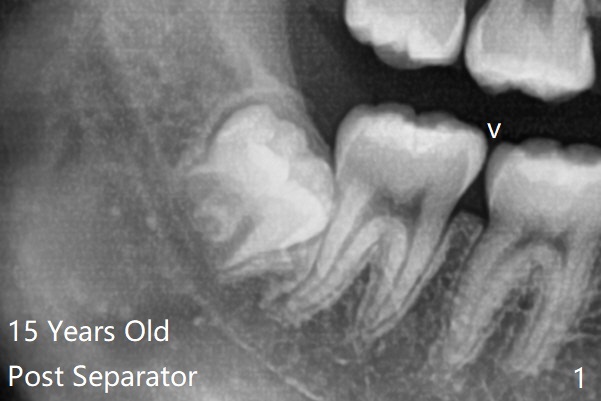

1.5年智齿牙根长长(图二)。1.5月后下颌智齿拔除放置Osteogen Plug(图三)。